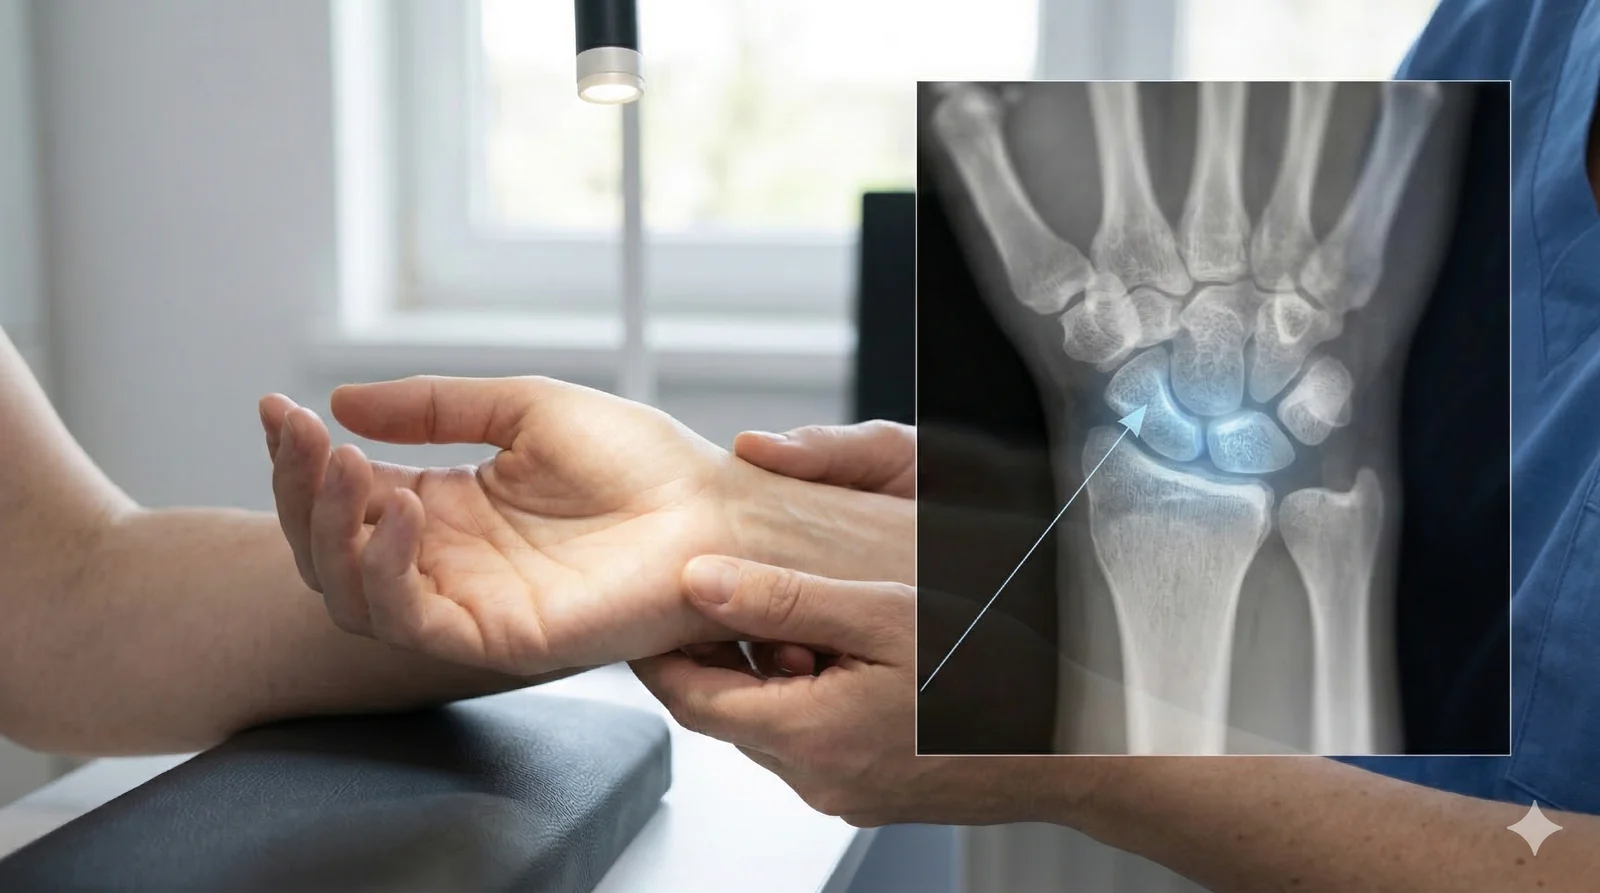

Przewlekły ból nadgarstka – kiedy przyczyną może być choroba Kienböcka?

Przewlekły ból nadgarstka bywa trudny do jednoznacznego rozpoznania. U części pacjentów dolegliwości utrzymują się miesiącami, a czasem nawet latami, mimo leczenia zachowawczego i wykonywanych badań obrazowych.

Jedną z możliwych przyczyn jest choroba Kienböcka – schorzenie polegające na zaburzeniu ukrwienia kości księżycowatej nadgarstka. We wczesnym stadium objawy mogą być niespecyficzne, a pierwsze badanie RTG nie zawsze wykazuje zmiany. Z tego powodu pacjenci często przez długi czas leczą się z powodu przeciążenia lub nieswoistego bólu nadgarstka.

Właściwe rozpoznanie pozwala zaplanować leczenie na etapie, gdy rokowanie jest zdecydowanie najlepsze.